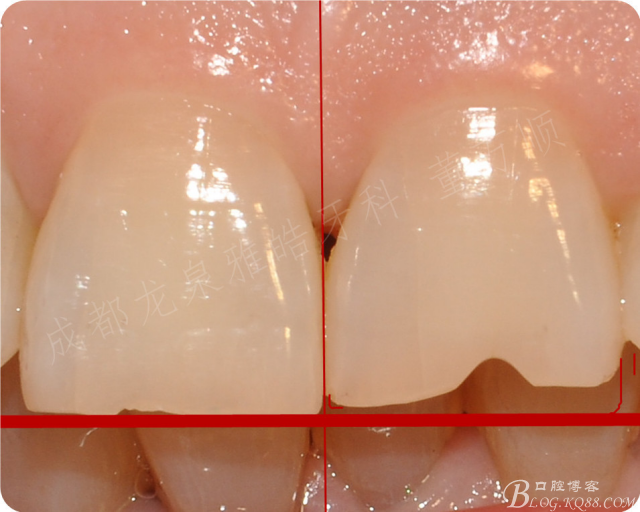

患者要求改善前牙美观

一定要 左右对称,拒绝烤瓷冠修复(之前咨询的单位应该都建议全瓷冠修复)

后来沟通 树脂充填 或瓷贴面修复

相对树脂修复,瓷贴面修复一样的 微创,但是 使用寿命 后期维护相对树脂会 更具优势

牙体预备 没有用局麻的

过程完全无痛

树脂点酸蚀 临时贴面(方便快捷)

修复完成后 基本达到了患者的要求